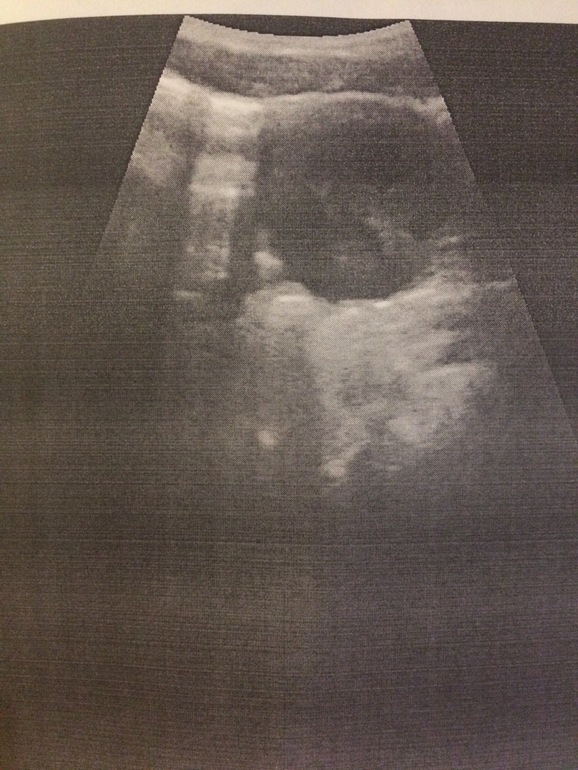

В понедельник поеду в другую клинику на УЗИ у них вроде новые оборудования ,может ,что-то конкретнее скажут.Снимок яичника который мне сделали

Второе, по снимку УЗИ: контуры яичника четкие, не ровные, однородность нарушена. Это не ЖТ и не киста. Больше похоже на воспаление. Свободная жидкость есть в позадиматочном?